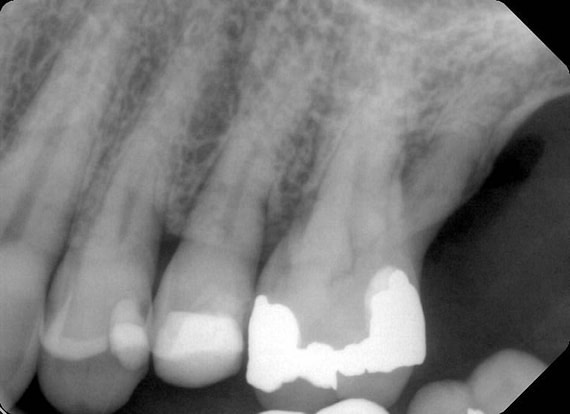

Over the years, the patient had experienced multiple cracked teeth, which had led to various complications and treatments. In 2021, the patient reported hearing a loud crack while eating, after which tooth 24 became tender to biting pressure.

Upon examination by his previous dentist, a vertical root fracture was diagnosed, necessitating a surgical extraction. The procedure, which involved removing the buccal cortical bone, left the patient with a bony defect in the area of the extracted tooth.

Upon completing a comprehensive examination, it was revealed that teeth 25 and 26 were also cracked, and the patient expressed interest in replacing the missing tooth 24.

To better understand the patient's overall dental health, a full mouth CBCT scan was taken, confirming the presence of a bony defect in the area where tooth 24 had been surgically extracted.